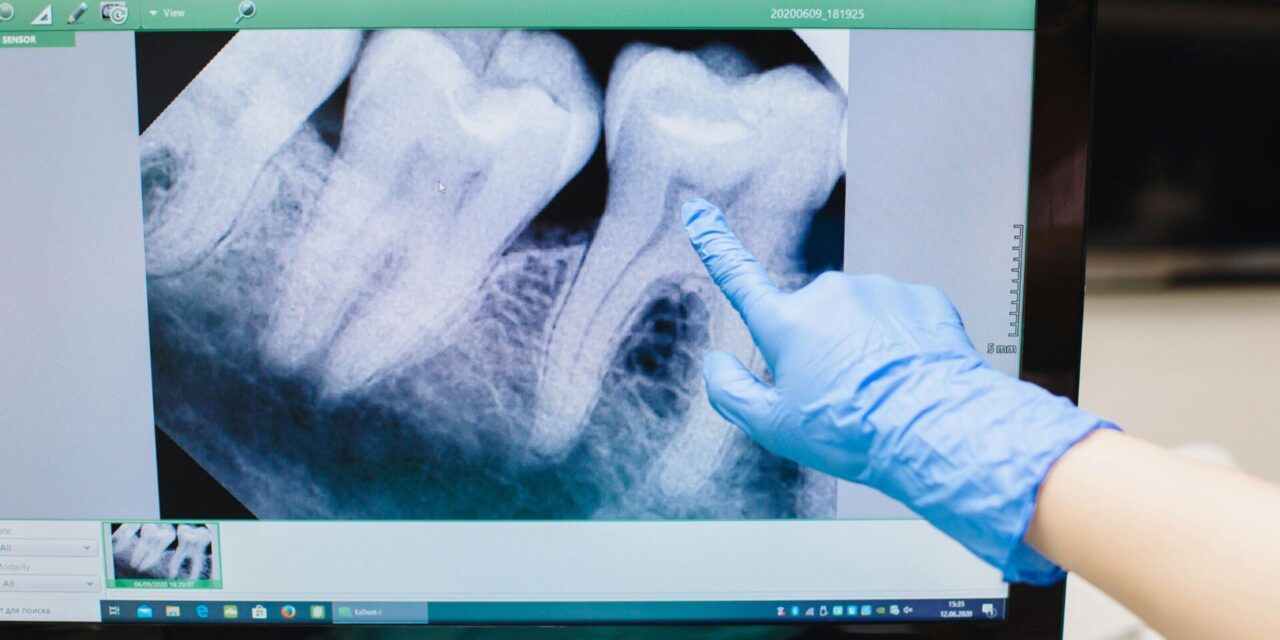

- Diagnóstico previo: Antes de cualquier extracción, se realizará una radiografía (generalmente una ortopantomografía y, en casos complejos, una tomografía CBCT 3D) para evaluar la posición de la muela, su relación con los nervios y las raíces de los dientes adyacentes.

Es crucial elegir a profesionales experimentados en cirugía oral. La evaluación preoperatoria detallada, que incluye radiografías, permite identificar y minimizar estos riesgos.

- Tecnología de la clínica: Una clínica moderna debe contar con radiografías digitales de última generación, como la ortopantomografía o el CBCT 3D, que ofrecen imágenes precisas para una planificación detallada de la extracción.